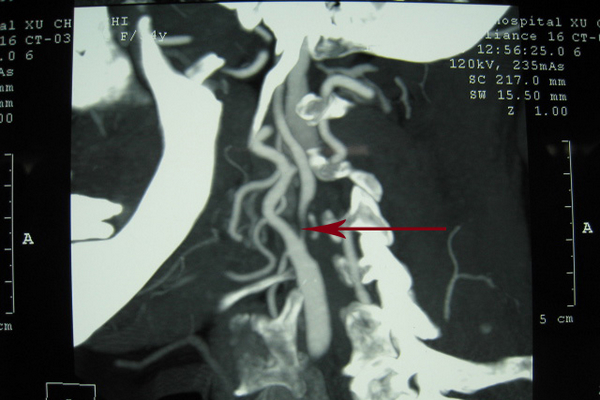

CT——颈总动脉末端及颈内、颈外动脉起始段重度狭窄